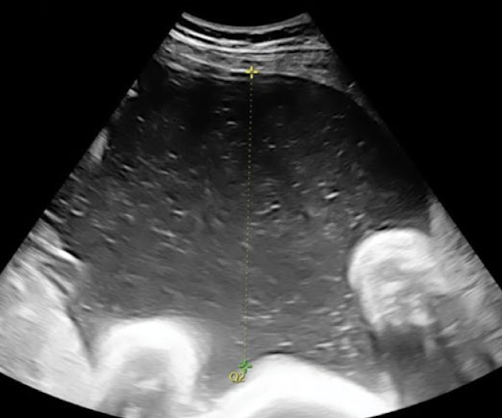

AF measurement method: subjective

“eyeball” assessment of amount of fluid

no actual measurements

better used early in gestation

successful with more experienced sonographer

leads to a more quantitative assessment

which has subjectively less AF?

right image